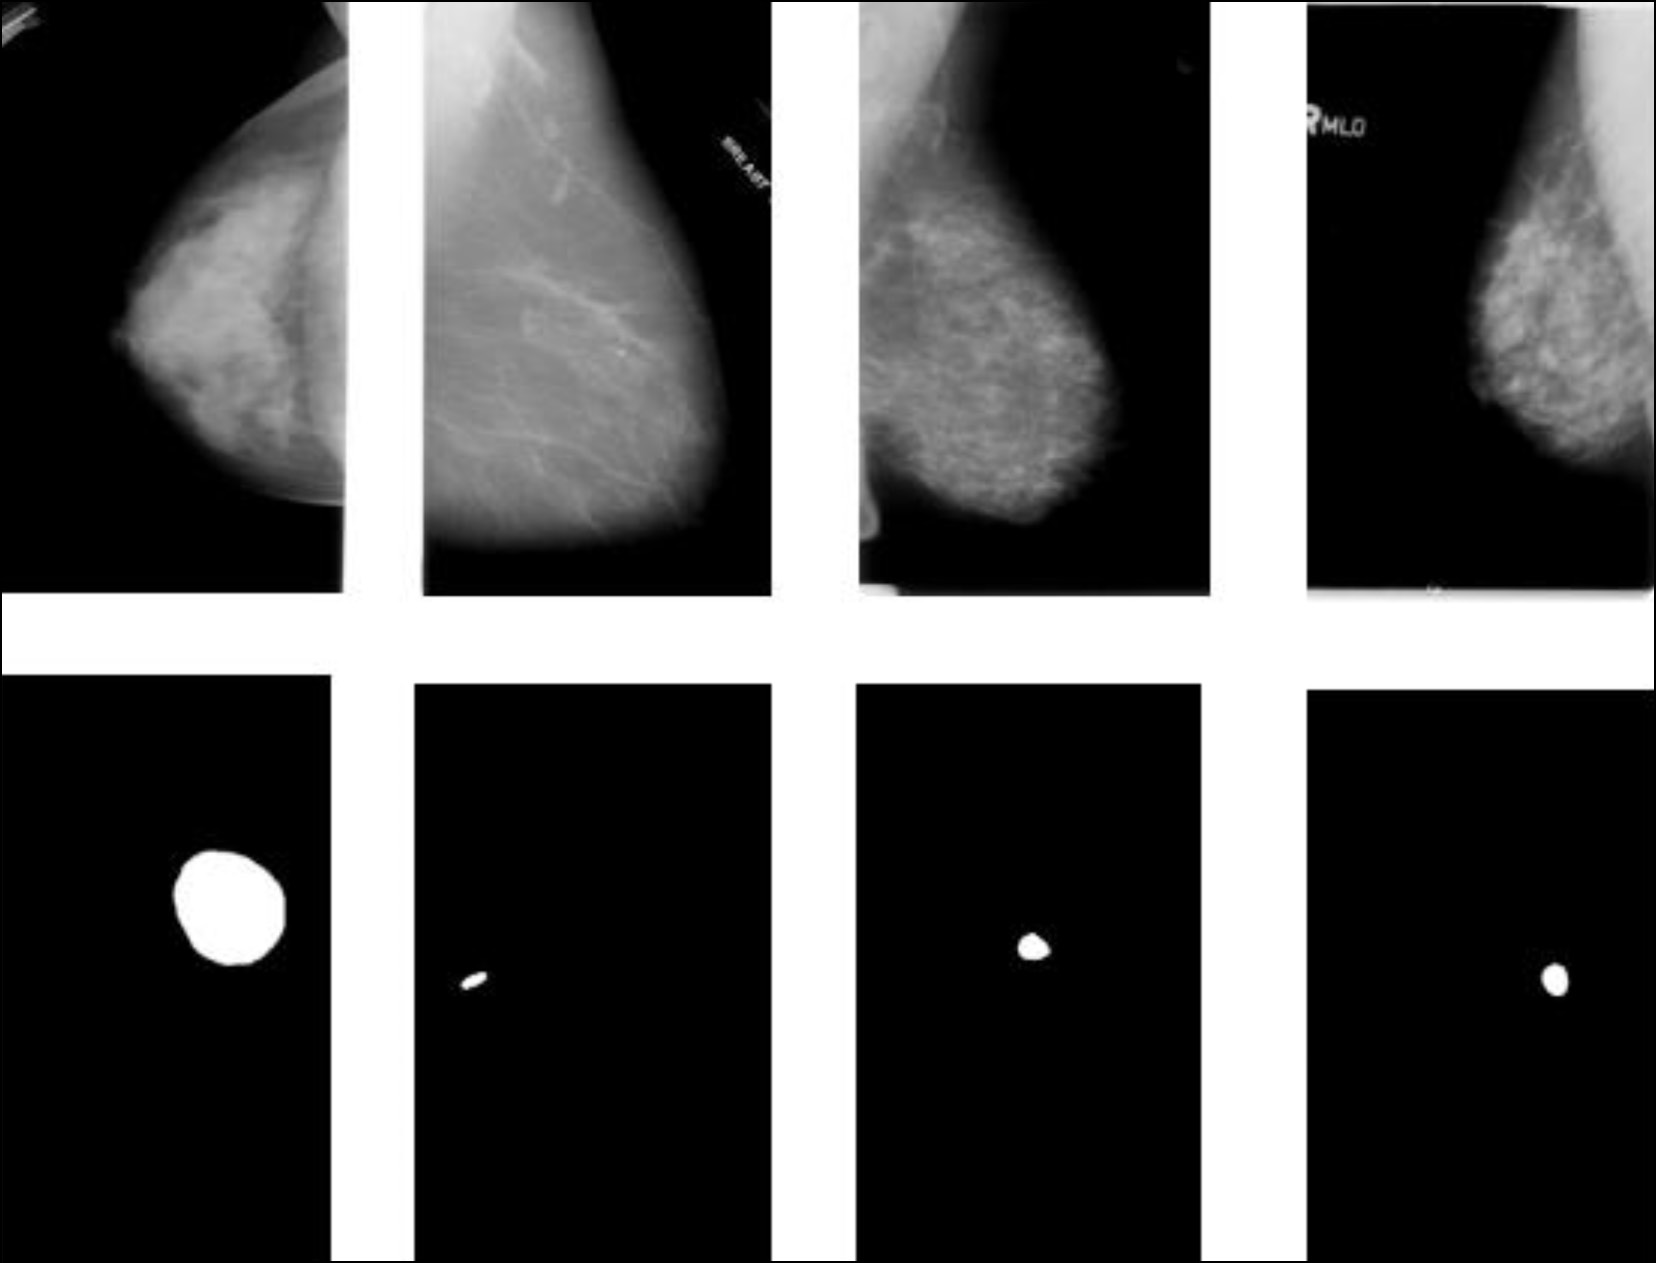

Machine learning techniques for breast cancer diagnosis

Abstract

In the last few years, machine learning techniques have been attracting even greater attention in the field of diagnostics, particularly when detecting breast cancer. Relevant studies dedicated to machine learning techniques in breast cancer diagnosis were analyzed in three areas: solving secondary problems that occur in modern-day breast cancer diagnostics, role in an intelligent assessment of the patient’s condition for preliminary diagnostic decisions, and capability to detect breast cancer risk factors. The results revealed that machine learning techniques applied in breast cancer diagnosis have great potential for improving diagnostic accuracy and efficiency and solving secondary problems. The medical literature analysis has determined the parameters that are used as input data in machine learning techniques. Furthermore, the collected information will be applied to create a parameter system for breast cancer diagnosis using machine learning techniques.